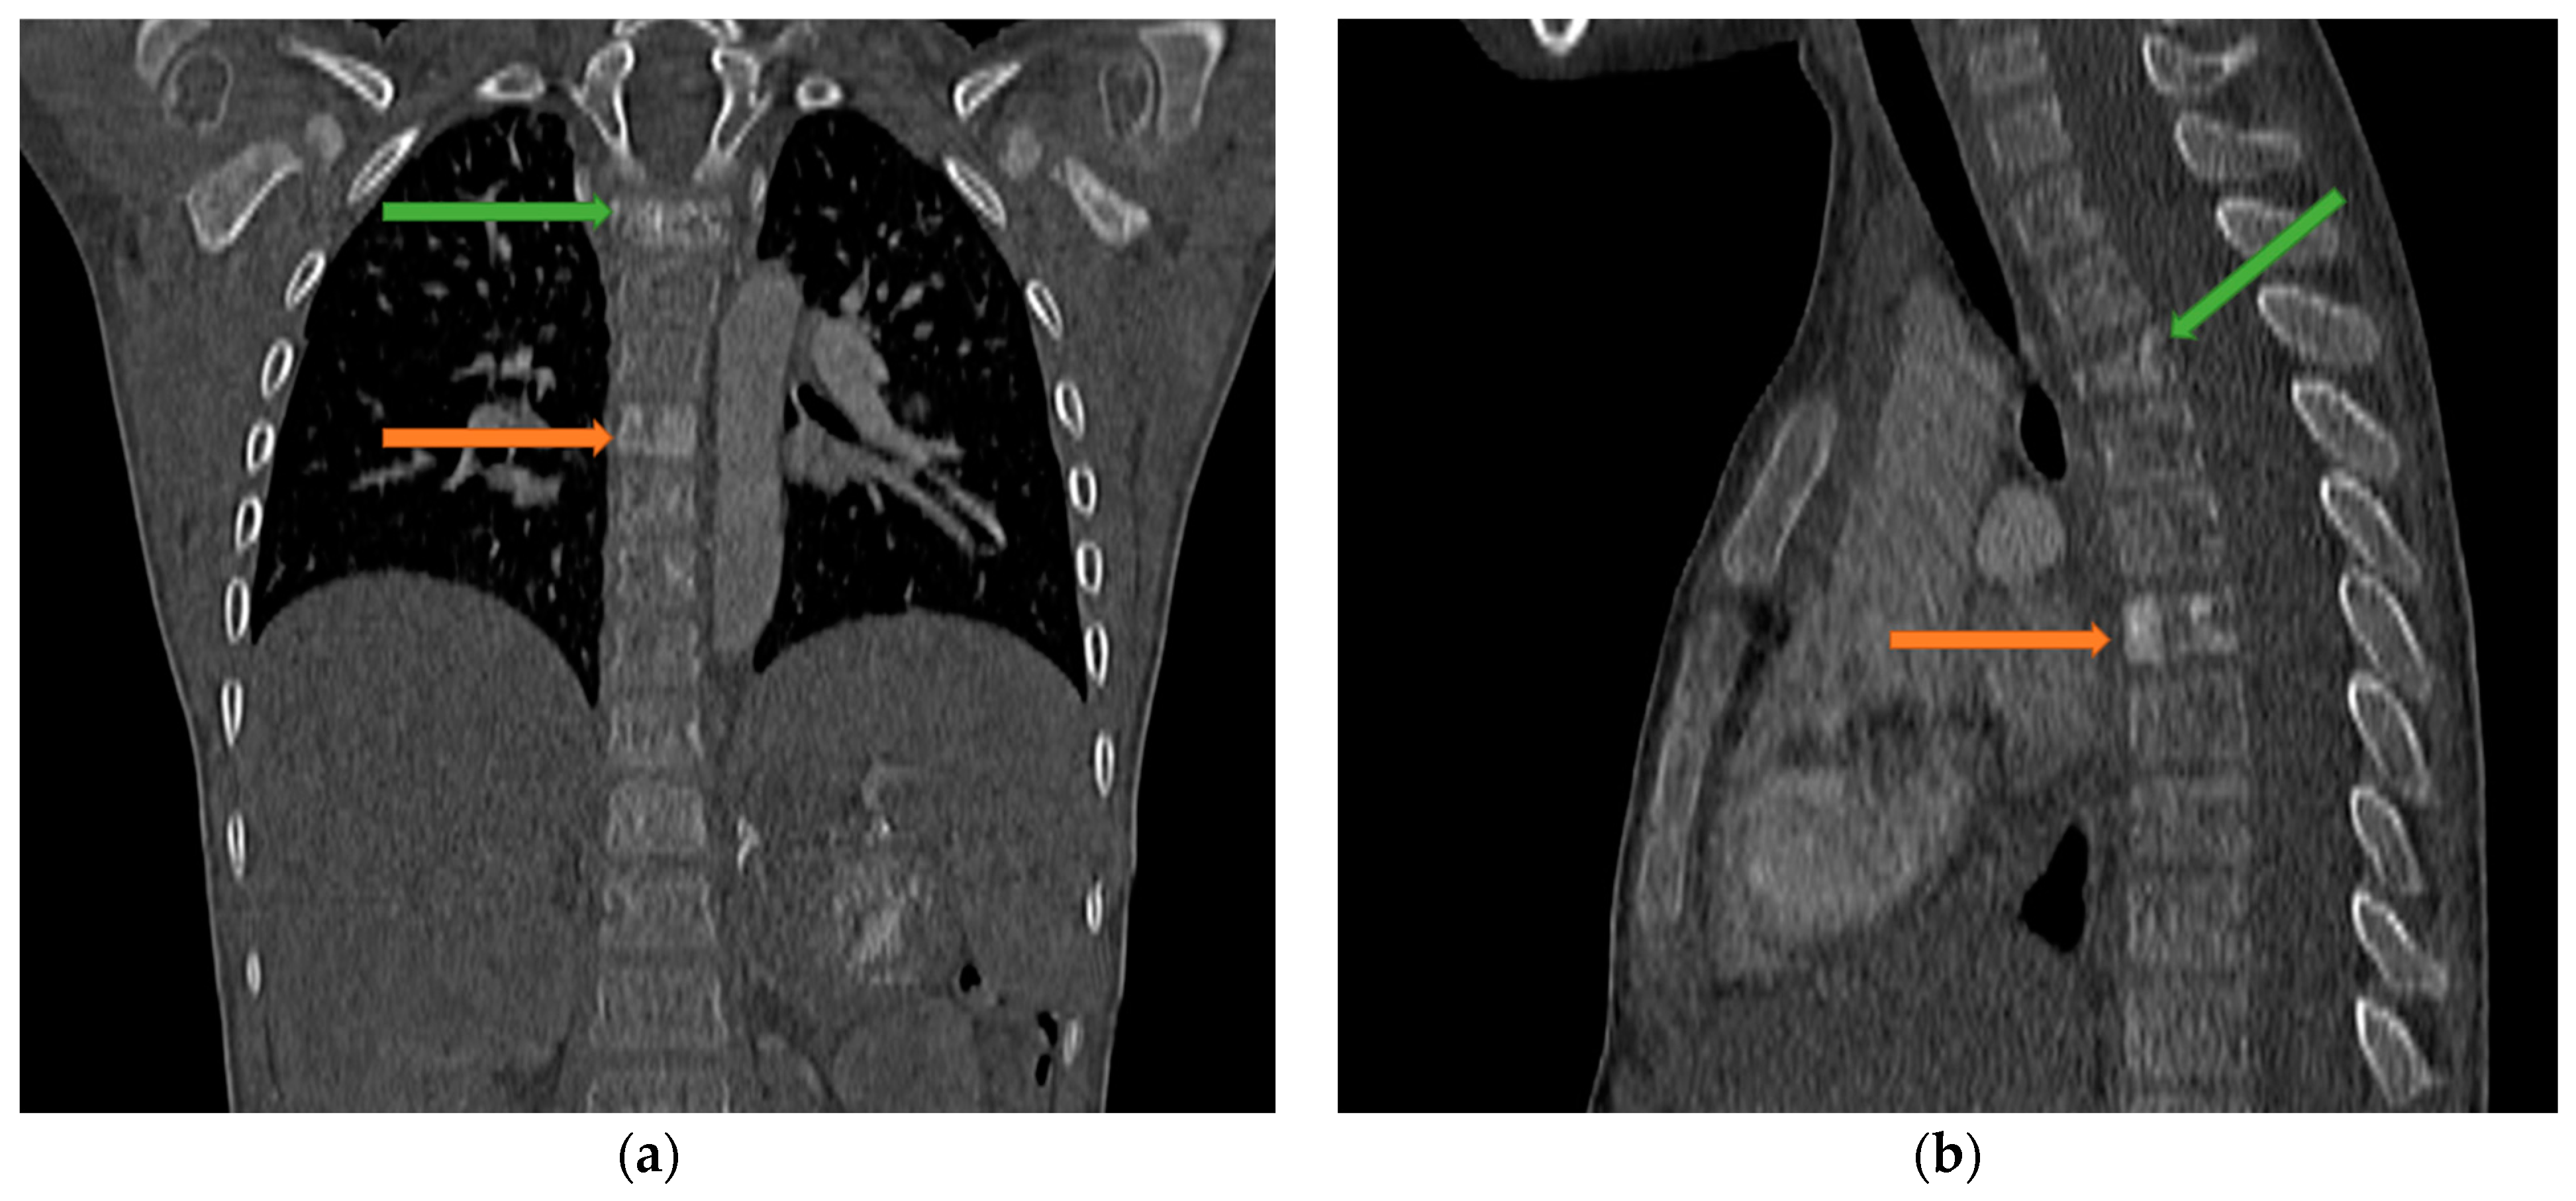

4. Case Presentation